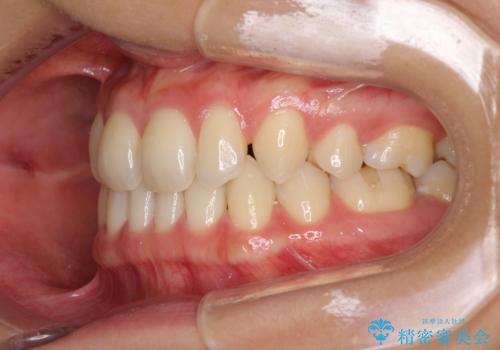

- 以前の矯正治療の後戻りにより、上の前歯にスペースができたことを気にして来院された患者様です。

インビザラインを用いて前歯のスペースを閉じつつ、上下の咬み合わせを構築していくこととしました。